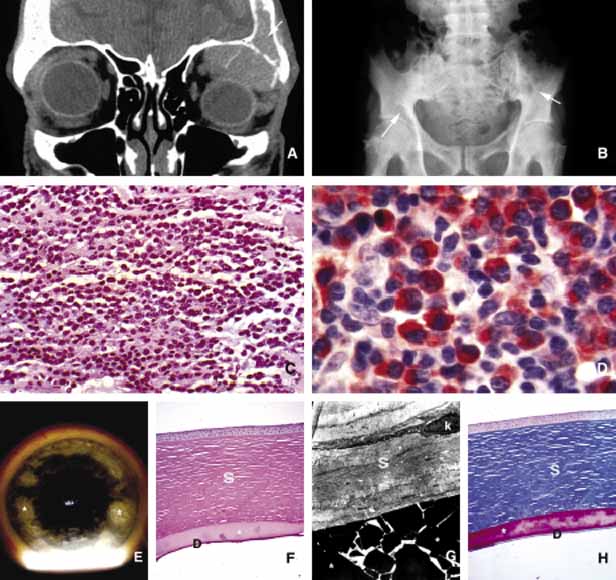

Sarcoid granulomas are made of epithelioid cells and multinucleated giant cells, surrounded by lymphocytes and occasional plasma cells (Fig. 11). Many inclusion bodies have been described in the giant cells of sarcoidosis but none of these is pathognomonic. The granulomatous response of sarcoidosis is rather typical but not unique for this entity; fungal diseases, tuberculosis, Crohn disease and leprosy may produce similar granulomas115 (Table 2).

Fig. 11 Sarcoidosis. The appearance of a large sarcoidosis granuloma involving the anterior orbit and periorbital skin (g). The central dome-like lesion is caused by secondary to a Staphylococcus infection. In addition, plaquoid skin lesions of sarcoidosis are seen above the left eyebrow, on the left upper eyelid, and on the periorbital skin (A). The T2-weighted axial MRI with contrast reveals bilateral enlargement of lacrimal glands (g) in another case B. Frames C and D show T1-weighted sagittal MRIs with localized granulomatous masses of sarcoidosis within the posterior orbit involving the apex and extending into the cavernous sinus (C, D). A well-delineated but not encapsulated mass of a sarcoid granuloma (E). The histopathology of sarcoidosis consists of multiple granulomas composed of histiocytic cells, chronic inflammatory cells, and multinucleated giant cells (g) (F).

Approximately one-fourth of sarcoidosis patients develop ocular and orbital manifestations including anterior and posterior uveitis, chorioretinitis, conjunctival and eyelid granulomas and orbital mass lesions (Fig. 11). Lacrimal gland is a common site of involvement; autopsy studies show a high percentage of microscopic disease; however, only 15% to 20% of the patients show clinical symptoms. Although virtually any part of the orbit may be involved with sarcoidosis, the most common site is the lacrimal fossa and the disease in this location may be confused with chronic dacryoadenitis, Sjögren syndrome, or space-occupying lesion. Sarcoid granulomas may also extend into the orbit from adjacent sinus mucosa.116 If other manifestations of the disease are absent, these cases may mimic secondary orbital tumors and they can only be differentiated by biopsy.

Patients with distinctive systemic manifestations with bilateral hilar lympadenopathy, skin lesions, uveitis, etc., usually show increased angiotensin-converting enzyme (ACE) levels.117 Serum lysozyme and calcium levels may also be increased in sarcoidosis but neither one of these tests is specific for the disease. The ultimate diagnosis is by biopsy. Some advocate to perform biopsy only on the sarcoid-suspect lesions such as skin and conjunctival nodules in which the yield is usually rewarding. Others support random “blind” biopsy of the conjunctiva in sarcoid suspects. The yield of random biopsy without a distinct lesion is rather low (approximately 25% positive), but the conjunctival biopsy carries low morbidity and can be inexpensively and quickly performed in the clinic, as opposed to more invasive biopsies of transbroncheal lymph nodes, liver, and orbit. It is advisable, from the practical standpoint, to biopsy the conjunctiva randomly early in the workup of a sarcoidosis-suspect patient.118 If the biopsy result reveals granulomatous inflammation, more invasive procedures with high morbidity and cost can be avoided.

The involvement of the optic nerve with sarcoidosis is usually an anterior process and associated with typical retinal vasculitis, however, the optic nerve involvement may rarely extend posteriorly and form a mass lesion.119

The treatment of sarcoidosis is directed to the systemic disease. Surgery may be necessary to biopsy or debulk orbital lesions if there is a need for histopathologic evaluation in patients with no other easily accessible biopsy sites. In few instances, the orbital disease presents with no history or detectable symptoms of systemic sarcoidosis (Fig. 11). In these patients, sarcoidosis is usually a surprising diagnosis obtained from an orbital “tumor.” The mainstay of treatment is the use of systemic corticosteroids and antimetabolites such as methotrexate.